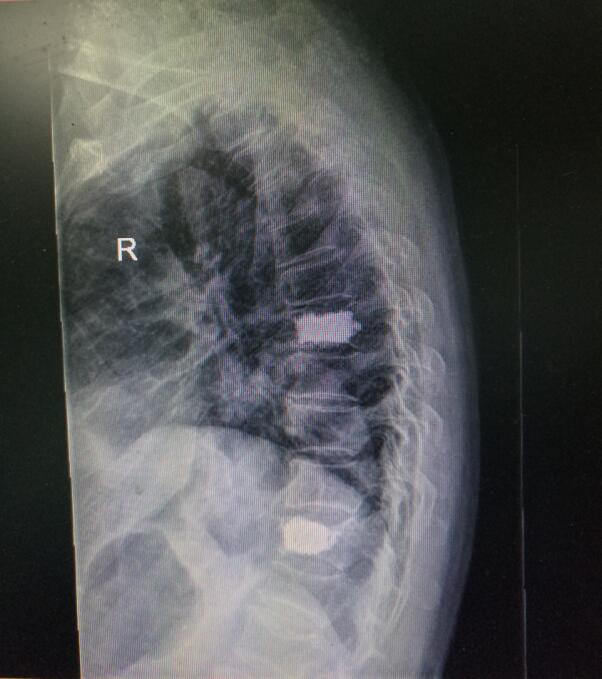

術(shù)前DR(數(shù)字化的x射線)

入院后第四天,由骨傷二科副主任楊陳一、劉永森醫(yī)生、唐國皓醫(yī)生聯(lián)合為患者成功實(shí)施了微創(chuàng)下的經(jīng)皮穿刺椎體后凸成形術(shù)。術(shù)后,患者腰背部疼痛逐漸緩解,術(shù)后第二天即下床活動(dòng)。

術(shù)后DR(數(shù)字化的x射線)